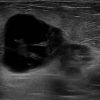

Ung thư vú

» Thông tin: Nữ giới – 55 tuổi.

» Lâm sàng: Khối tuyến vú.